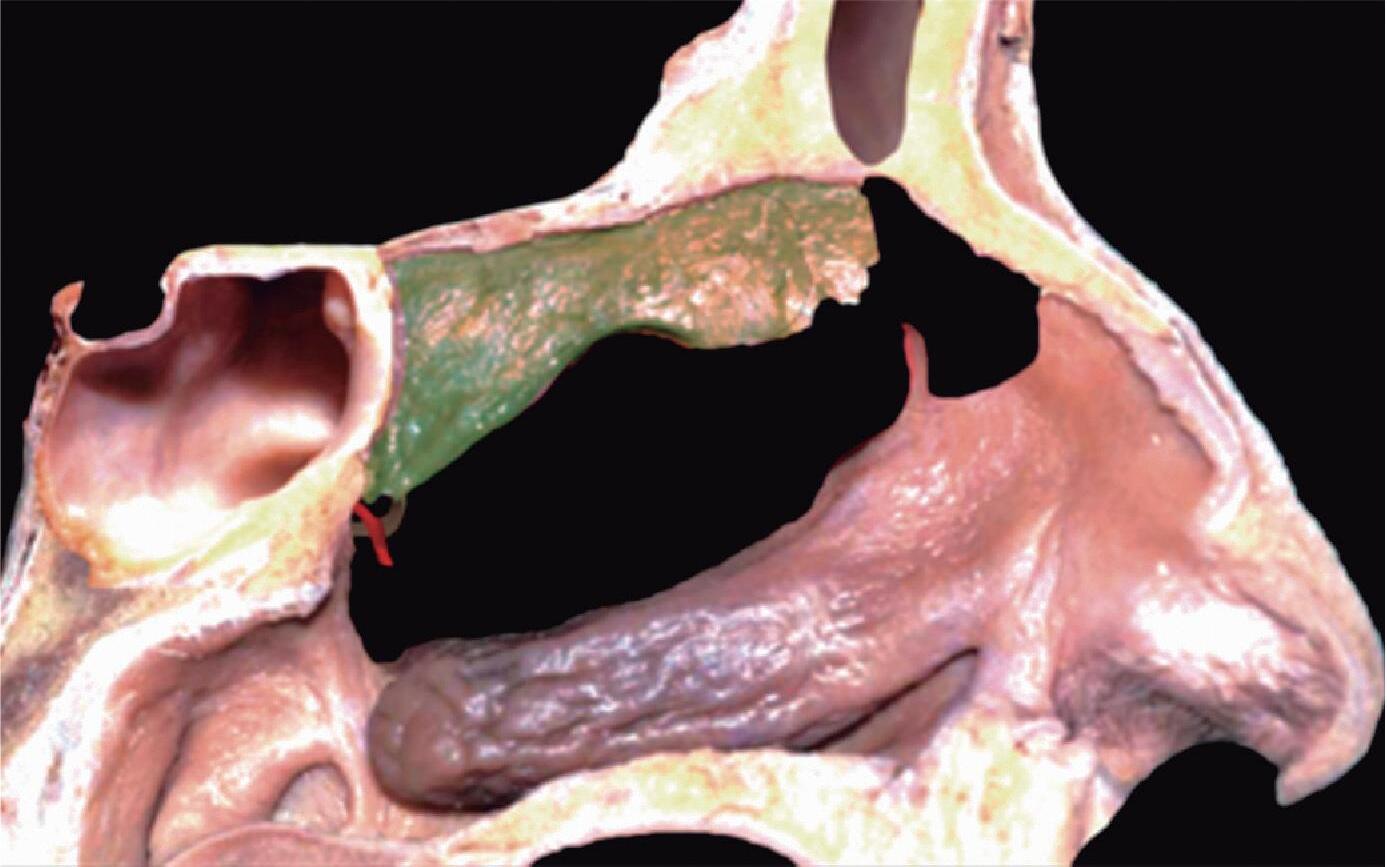

Fig. 1-20. Reconstrução tridimensional de TC demonstrando a lamela basal situada posteriormente à bulha etmoidal, acoplada à parede medial da órbita, fechando a câmara anterior: verde – concha média; vermelho – bulha etmoidal; amarelo – parede medial da órbita; lilás – processo uncinado.